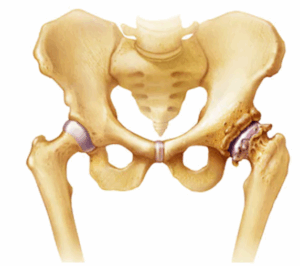

Bone spurs

Bone spurs are bony growths that form along bone edges. They're also called osteophytes. Bone spurs often form where bones meet each other — in the joints. They also can form on the bones of the spine.